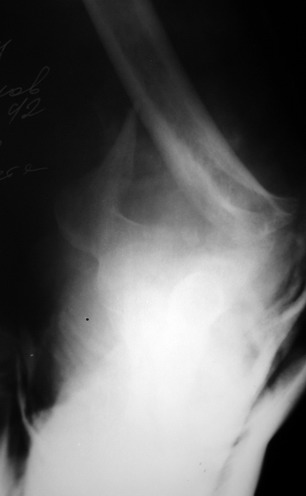

Уважаемые коллеги! Мужчина, 28 лет. 1 сутки назад получил бытовую травму - закрытый чрезмыщелковый перелом правой плечевой кости со смещением. По месту жительства в ЦРБ - репозиция, иммобилизация. Направлен к нам.

Солидарен с мнением обоих Александров (Челнокова и Рыкова): точную репозицию такого перелома вряд ли удастся выполнить закрыто. Даже во время открытого вмешательства это сделать непросто. Неслучайно предложен костно-пластический доступ с временным отсечением локтевого отростка. И по методу фиксации согласен с Александром Челноковым: 2 пластины. В качестве примера привожу рентгенограммы одного из наших пациентов с аналогичным повреждением.